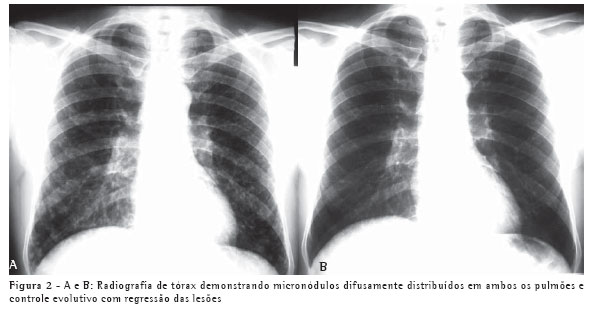

Um paciente, do sexo masculino, branco, de 67 anos, procedente de Blumenau (SC), representante de vendas, iniciou quadro de dispnéia, astenia, dor torácica e sudorese dez dias após limpeza do forro da sua casa, onde estão localizadas caixas d'água. Esteve em contato com fezes de morcego por tempo limitado, enquanto o local era varrido. A presença de nódulos pulmonares em radiografia e tomografia de tórax (Figuras 1A e 1B) e a ausência de expectoração justificaram a realização de biópsia de nódulopulmonar.

conhecimento das síndromes clínicas e a suspeição clínica podem evitar o tratamento empírico. Os achados radiológicos, os exames negativos e a alta freqüência da tuberculose em nosso meio foram os fatores para o tratamento para tuberculose nos dois pacientes. O teste de imunodifusão, embora negativo nestes dois pacientes, tem alta sensibilidade, sendo positivo em aproximadamente 75% dos casos.(6) O tempo de exposição ao inóculo determina a gravidade da doença. Isto explica o fato de o segundo paciente, que varreu o local, ter apresentado uma forma mais grave da doença, com alteração radiológica pulmonar difusa e necessidade de hospitalização. Por outro lado, uma pequena exposição determina lesões pulmonares focais, como no caso 1.